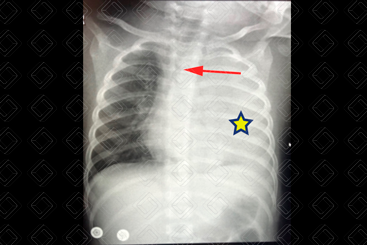

Texto alternativo para a imagem Figura 3. Créditos: Dra. Elazir Mota - Rio de Janeiro/RJ

Descrição da figura 3: Caso 2: Radiografia de tórax AP, evidenciando hemitórax opaco à esquerda (asterisco). Ao olhar com atenção a radiografia, observa-se que o hemitórax acometido tem volume aumentado em comparação ao contralateral, com discreto desvio da traqueia para a direita (seta vermelha). Estamos diante de um hemitórax opaco com aumento volumétrico do lado acometido. O passo seguinte foi solicitar uma ultrassonografia de tórax (figuras 4 e 5).